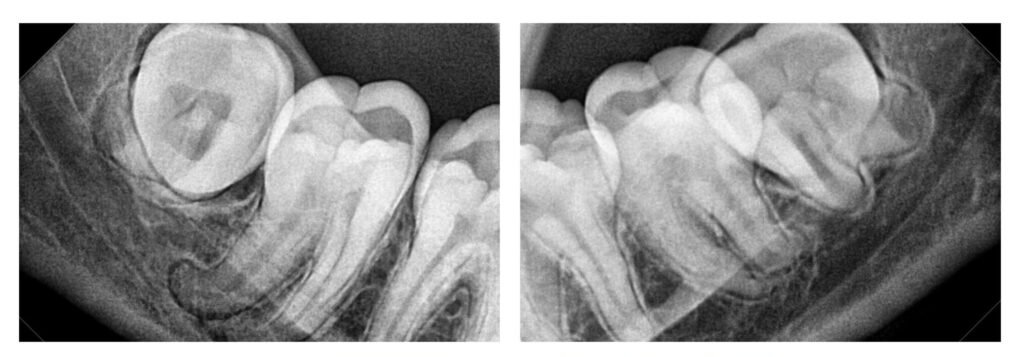

شكل ضرس العقل المدفون

ضرس العقل المدفون قد يظهر بأشكال مختلفة حسب وضعه وزاوية نموه في الفك. عمومًا، قد يكون لديك ضرس عقل مدفون إذا كان جزء كبير منه مختبئًا داخل اللثة أو العظم ولم يتمكن من الانبثاق بشكل صحيح في الفم. الصورة التالية هي رسمة توضيحية لشكل ضرس العقل المدفون جزئياً.